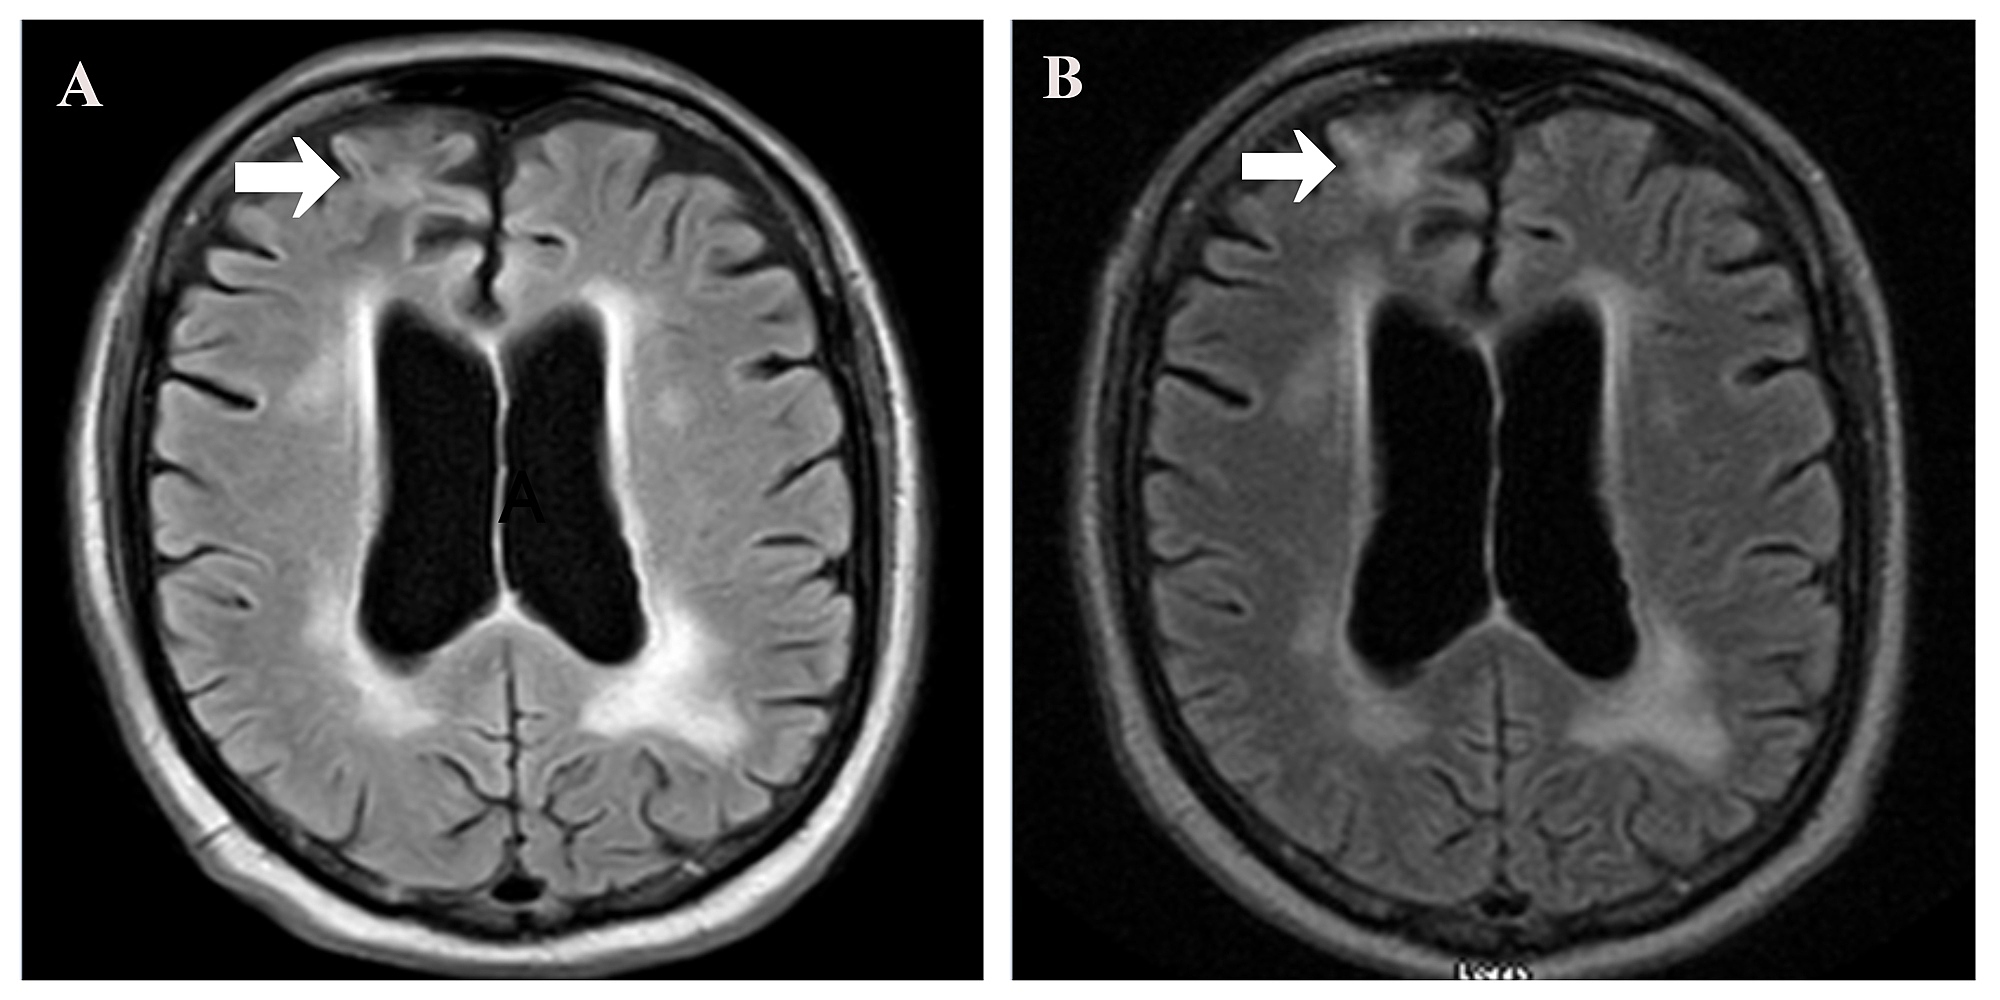

Figure 2 from Efficacy of Pembrolizumab and Nivolumab in Crossing the Pembrolizumab Blood Brain Barrier Various emerging strategies for permeability regulation and bbb crossing including passive transcytosis, intranasal. Increasing knowledge regarding the presence of a cns lymphatic system and the physical and biochemical alteration of the blood. In this article, we present the available evidence regarding the interactions between the immune system. Pembrolizumab Blood Brain Barrier.

(PDF) Efficacy of Pembrolizumab and Nivolumab in Crossing the Blood Pembrolizumab Blood Brain Barrier Increasing knowledge regarding the presence of a cns lymphatic system and the physical and biochemical alteration of the blood. Various emerging strategies for permeability regulation and bbb crossing including passive transcytosis, intranasal. In this article, we present the available evidence regarding the interactions between the immune system. Pembrolizumab Blood Brain Barrier.

Cureus Efficacy of Pembrolizumab and Nivolumab in Crossing the Blood Pembrolizumab Blood Brain Barrier In this article, we present the available evidence regarding the interactions between the immune system. Increasing knowledge regarding the presence of a cns lymphatic system and the physical and biochemical alteration of the blood. Various emerging strategies for permeability regulation and bbb crossing including passive transcytosis, intranasal. Pembrolizumab Blood Brain Barrier.